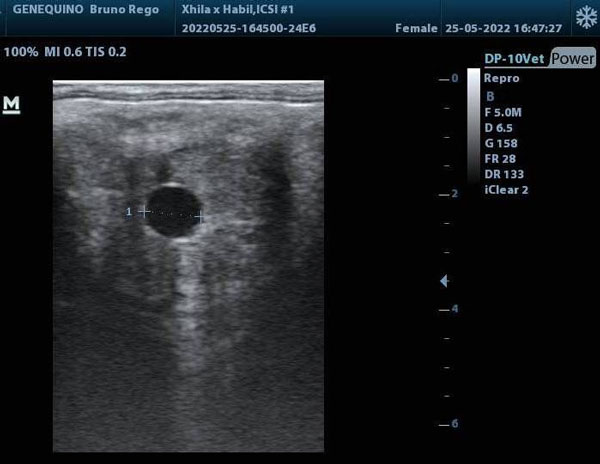

A Coudelaria Rio Lima recebeu recentemente a boa notícia de que um dos embriões congelados da sua égua Xhila resultou em gestação, no Centro de Reprodução Genequino.

Após 7-8 dias os embriões que tenham atingido o estádio de blastocisto serão congelados, e enviados para o Centro de Reprodução, onde mais tarde serão transferidos para uma égua receptora.